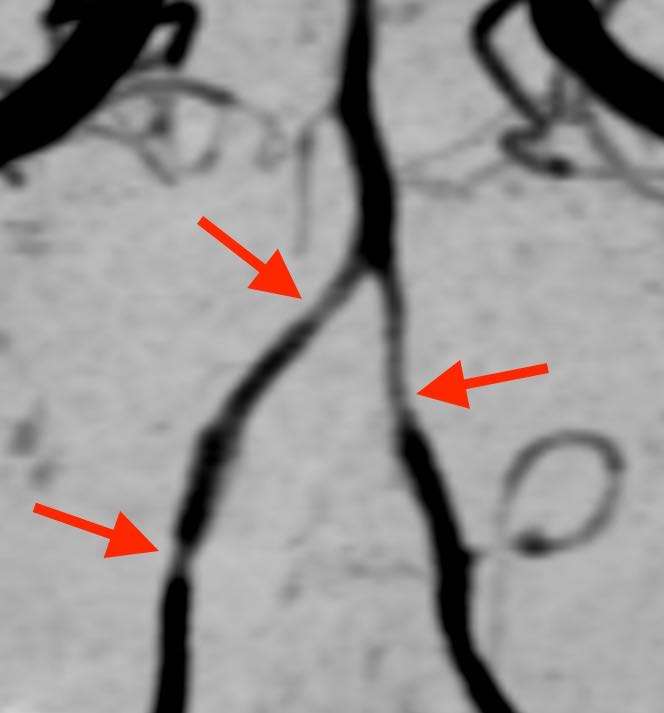

頭部MRA検査(MRIを用いた血管撮影)を撮ると、

夜中に頭痛で目が覚める

このように、脳の血管が所々で収縮して細くなっている状態が観察されます。まれに脳梗塞やくも膜下出血を合併する事があります。